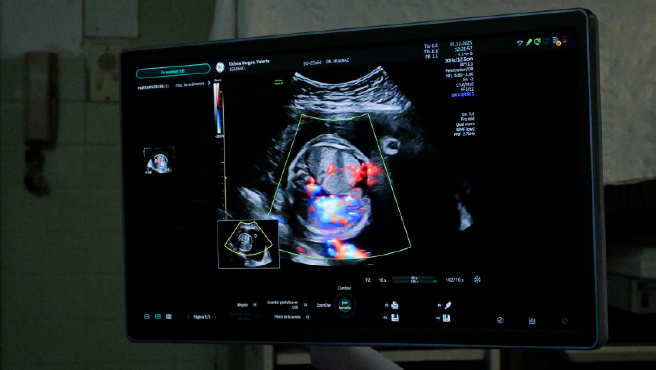

La anomalía fue detectada durante una ecografía morfológica realizada a la gestante Valery Ochoa Vargas, de 22 años, en el hospital Dos de Mayo, donde una evaluación especializada confirmó la gravedad del diagnóstico fetal.

En tanto, el jefe de la Unidad de Cirugía Fetal, Dr. Rubén Huaraz Zuloaga, explicó que el feto de 26 semanas presentaba un tumor de gran tamaño en el pulmón izquierdo. Esta condición había provocado acumulación de líquido, desplazamiento del mediastino y compresión pulmonar severa, lo que impedía su desarrollo normal. De no haberse intervenido de manera oportuna, advirtió, el desenlace habría sido la muerte fetal intrauterina.

El procedimiento se llevó a cabo en la sala de cirugía fetal bajo guía ecográfica permanente. Primero se coloca anestesia fetal intramuscular para que el feto no sienta dolor y se mantenga bien posicionado durante la cirugía, luego se introduce una aguja trocar de 18 gauge a través del abdomen materno en dirección a los vasos nutricios del tumor, se ingresa con la aguja trócar cuidadosamente a través del útero, llegando hasta la pared torácica del feto e ingresando al tórax fetal hasta donde se encuentra el tumor. Aquí se identifican los vasos nutricios del secuestro broncopulmonar dependientes de la arteria aorta. Una vez posicionados se pasa a través de la aguja una delgada fibra de láser que llega hasta la zona de los vasos nutricios lugar donde se realiza la ablación de estos.

“La cirugía fetal es de altísimo riesgo, ya que se trabaja directamente dentro del tórax del feto. Cualquier imprecisión puede comprometer estructuras vitales. Afortunadamente, el procedimiento fue exitoso, logramos reducir el tamaño del tumor, al momento, a una tercera parte, el hidrops desapareció y los pulmones del feto recuperaron su desarrollo normal”, destacó nuestro cirujano fetal el Dr. Rubén Huaraz.